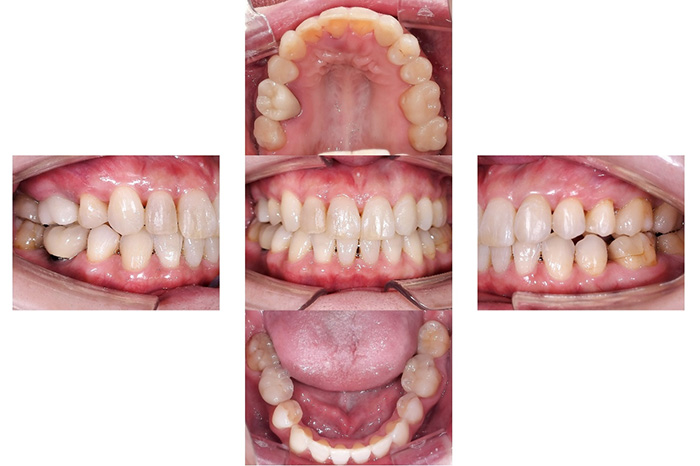

Before

After

以下の治療を組み合わせて行いました。

歯並びの改善と同時に、奥歯の咬合関係の改善を行っています。

右上臼歯部2本・左下臼歯部2本にインプラント治療を行った症例です。

欠損部に対しインプラントを埋入し、咀嚼機能の回復と咬合バランスの改善を行いました。周囲歯への負担を抑えながら、固定性のある補綴装置により安定した噛み心地を目指した治療です。

【右上臼歯部インプラント治療】インプラント埋入手術および上部構造装着(2本)

【左下臼歯部インプラント治療】インプラント埋入手術および上部構造装着(2本)

【右上臼歯部インプラント治療】約4か月

【左下臼歯部インプラント治療】約3か月

【右上臼歯部インプラント治療】8回

【左下臼歯部インプラント治療】8回

【右上臼歯部インプラント治療】1本 ¥555,500(税込)

※本症例は2本

【左下臼歯部インプラント治療】1本 ¥555,500(税込)